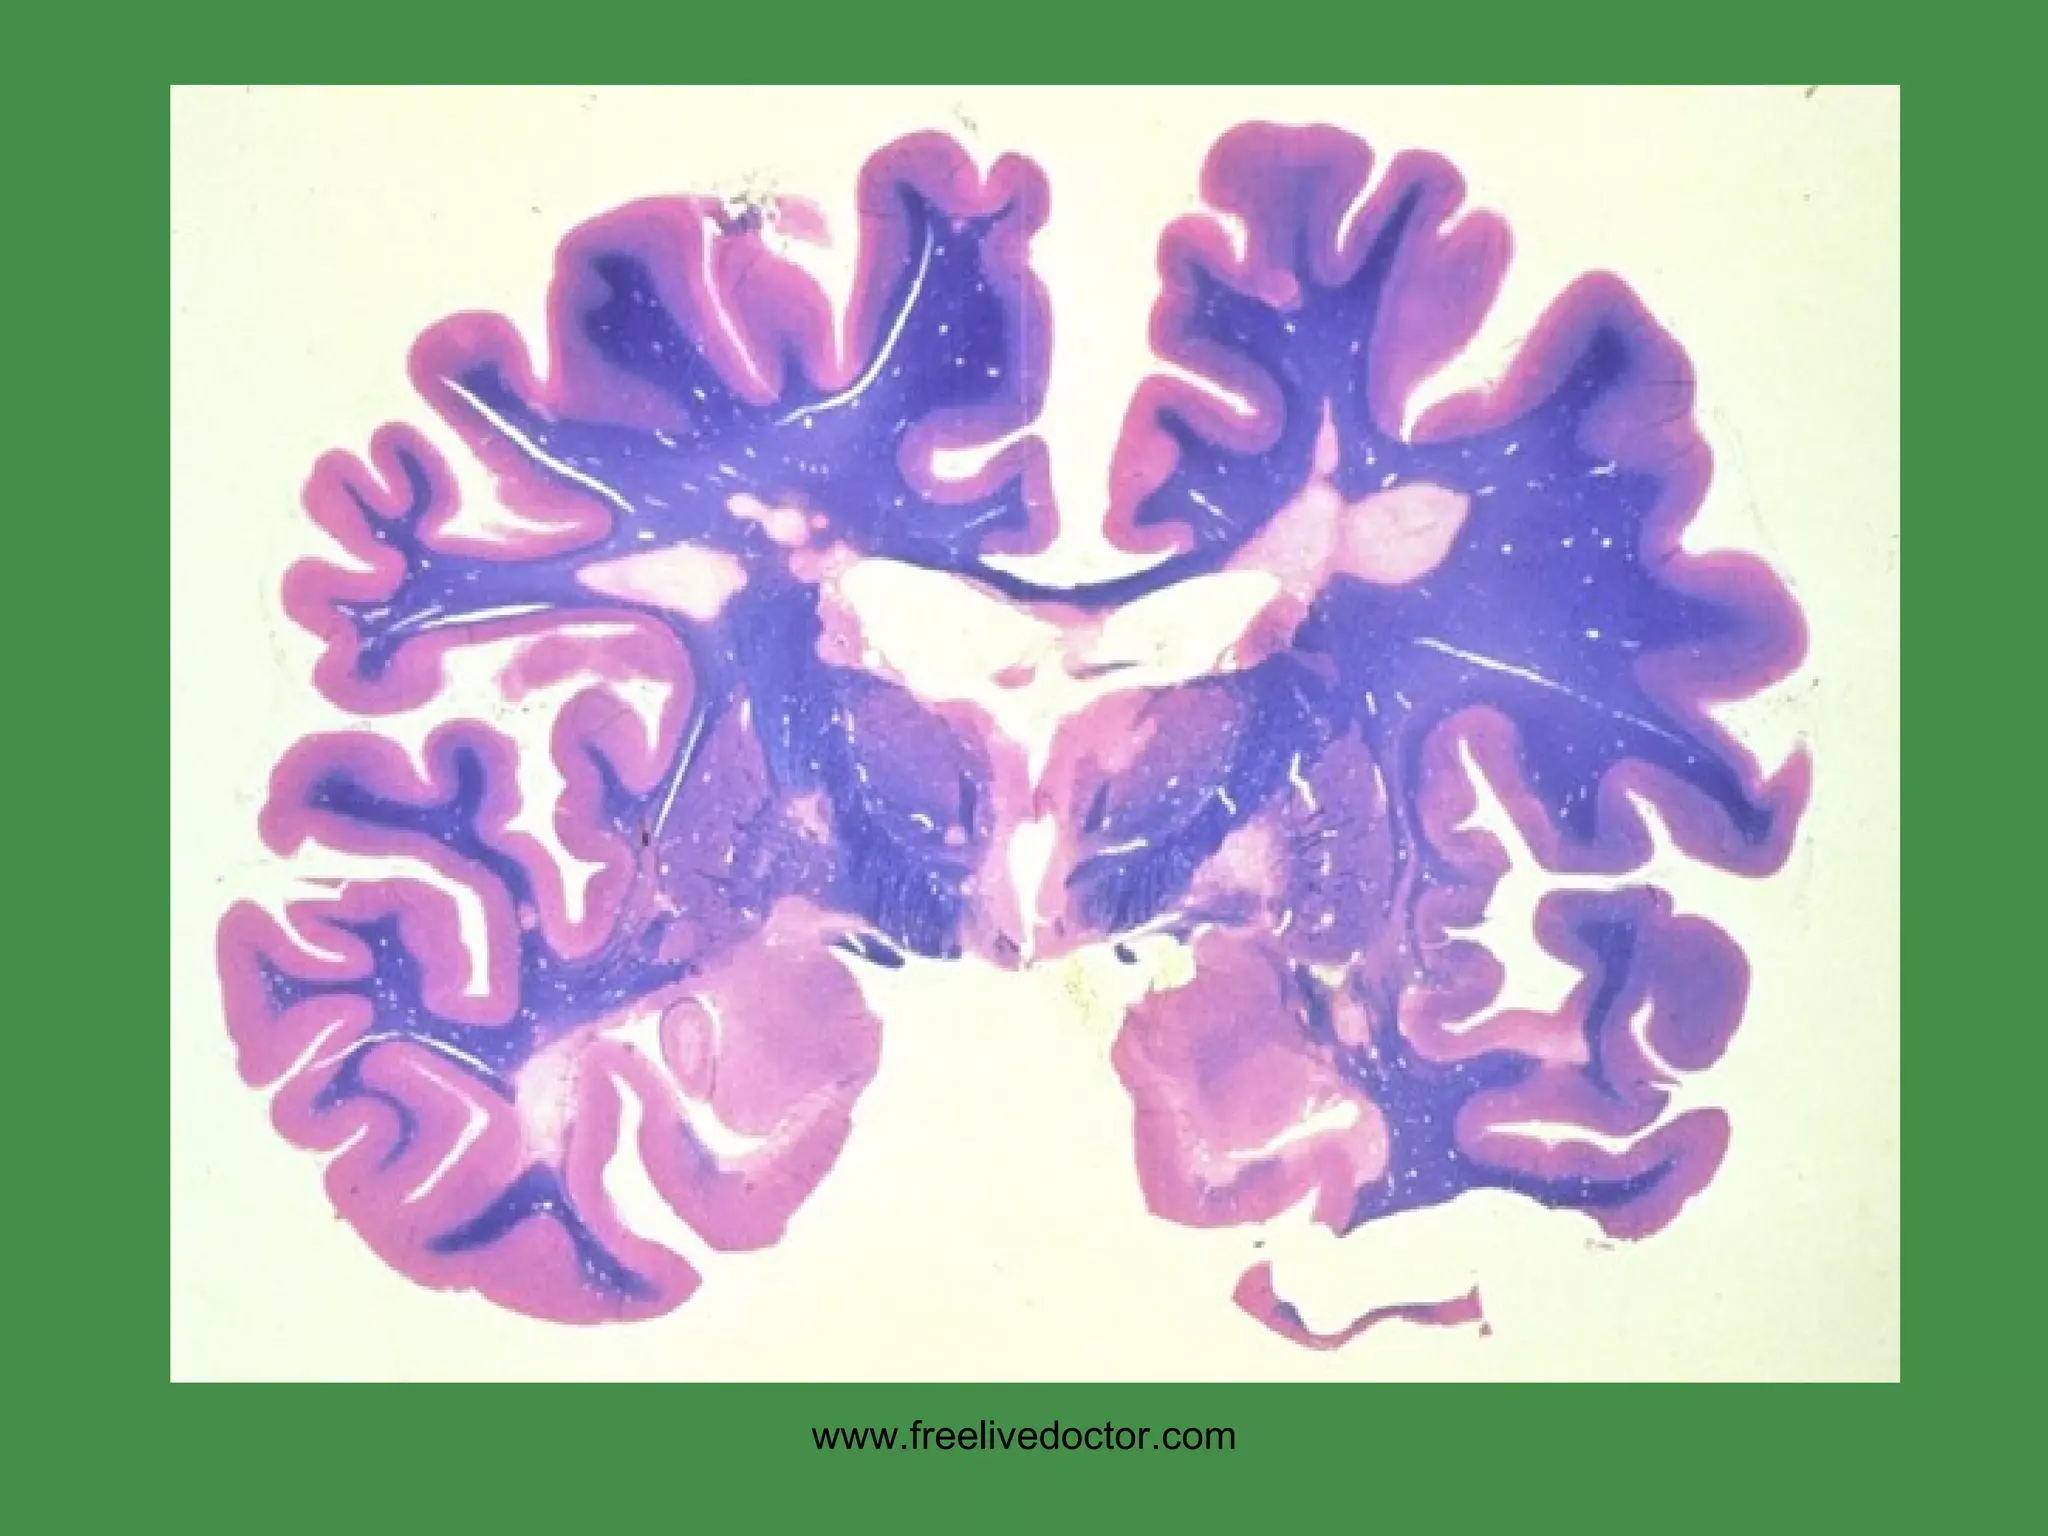

PLAQUES, MS www.freelivedoctor.com

www.freelivedoctor.com

• #108 Myelinated white matter stains BLUE, and demyelination is loss of blue. Remember MS is a disease PRIMARILLY of WHITE matter.

• #109 Plaques grossly

• #110 Plaques microscopically. Demyelination, edema, gliosis, and, lower right, relative preservation of the actual nerve fibers

MS Cause:  ? USA prevalence:  1:1000  F>>M,  Ages: 30’s, 40’s Immune response primarily against CNS myelin (white matter) Regional area of white matter demyelination is called “PLAQUE” Increased CSF gamma globulin, i.e., oligoclonal bands Often presents with VISUAL problems EXACERBATIONS/REMISSIONS www.freelivedoctor.com